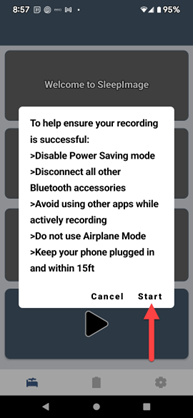

SLEEPIMAGE APP (Android)

SLEEPIMAGE APP (Android)

SLEEPIMAGE APP (Android)

SLEEPIMAGE APP (Android)

SLEEPIMAGE APP (Android)

SLEEPIMAGE APP (Android)

SLEEPIMAGE APP (Android)

SLEEPIMAGE APP (Android)

SLEEPIMAGE APP (Android)

SLEEPIMAGE APP (Android)

SLEEPIMAGE APP (Android)

SLEEPIMAGE APP (Android)

SLEEPIMAGE APP (Android)

SLEEPIMAGE APP (Android)

SLEEPIMAGE APP (Android)

SLEEPIMAGE APP (Android)

SLEEPIMAGE APP (Android)

SLEEPIMAGE APP (Android)

SLEEPIMAGE APP (Android)

SLEEPIMAGE APP (Android)

SLEEPIMAGE APP (iPhone)

SLEEPIMAGE APP (Android)

SLEEPIMAGE APP (Android)

SLEEPIMAGE APP (Android)

SLEEPIMAGE APP (Android)

SLEEPIMAGE APP (Android)

SLEEPIMAGE APP (Android)

SLEEPIMAGE APP (Android)

SLEEPIMAGE APP (Android)